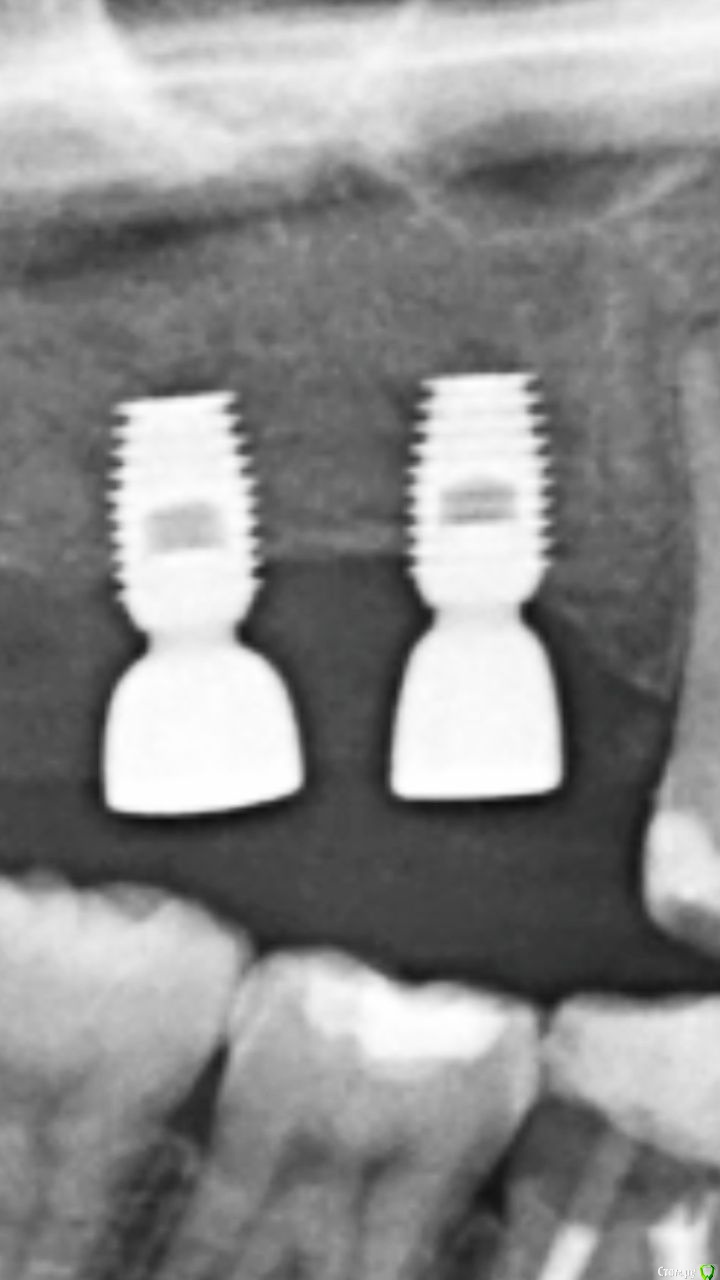

bazet Опубликовано 10 июля, 2019 Поделиться Опубликовано 10 июля, 2019 (изменено) Год назад установили импланты. Но чувствую неприятные ощущения , поэтому коронки не ставил. Вопрос можно ли ставить коронки ? Изменено 10 июля, 2019 пользователем bazet Ссылка на комментарий

bazet Опубликовано 10 июля, 2019 Автор Поделиться Опубликовано 10 июля, 2019 Фото во вложении Ссылка на комментарий

Pavel-Pskov Опубликовано 11 июля, 2019 Поделиться Опубликовано 11 июля, 2019 Вроде по снимкам всё ок, а какого плана неприятные ощущения? Ссылка на комментарий

колесников Опубликовано 14 июля, 2019 Поделиться Опубликовано 14 июля, 2019 Это байкон. Суть этого импланта,на плече платформы должна нарасти кость,а в вашем случае шейка и 2витка резьбы не покрыты костью. Будет периодически воспаляться десна. Обратитесь к вашему имплантологу,в таком состоянии протезирование не желательно 3 Ссылка на комментарий

Bier Опубликовано 18 июля, 2019 Поделиться Опубликовано 18 июля, 2019 выкручивать эти имплантаты надо. Ссылка на комментарий

red_butler Опубликовано 25 июля, 2019 Поделиться Опубликовано 25 июля, 2019 Обратитесь к вашему имплантологу,в таком состоянии протезирование не желательно выкручивать эти имплантаты надо. +1 Ссылка на комментарий